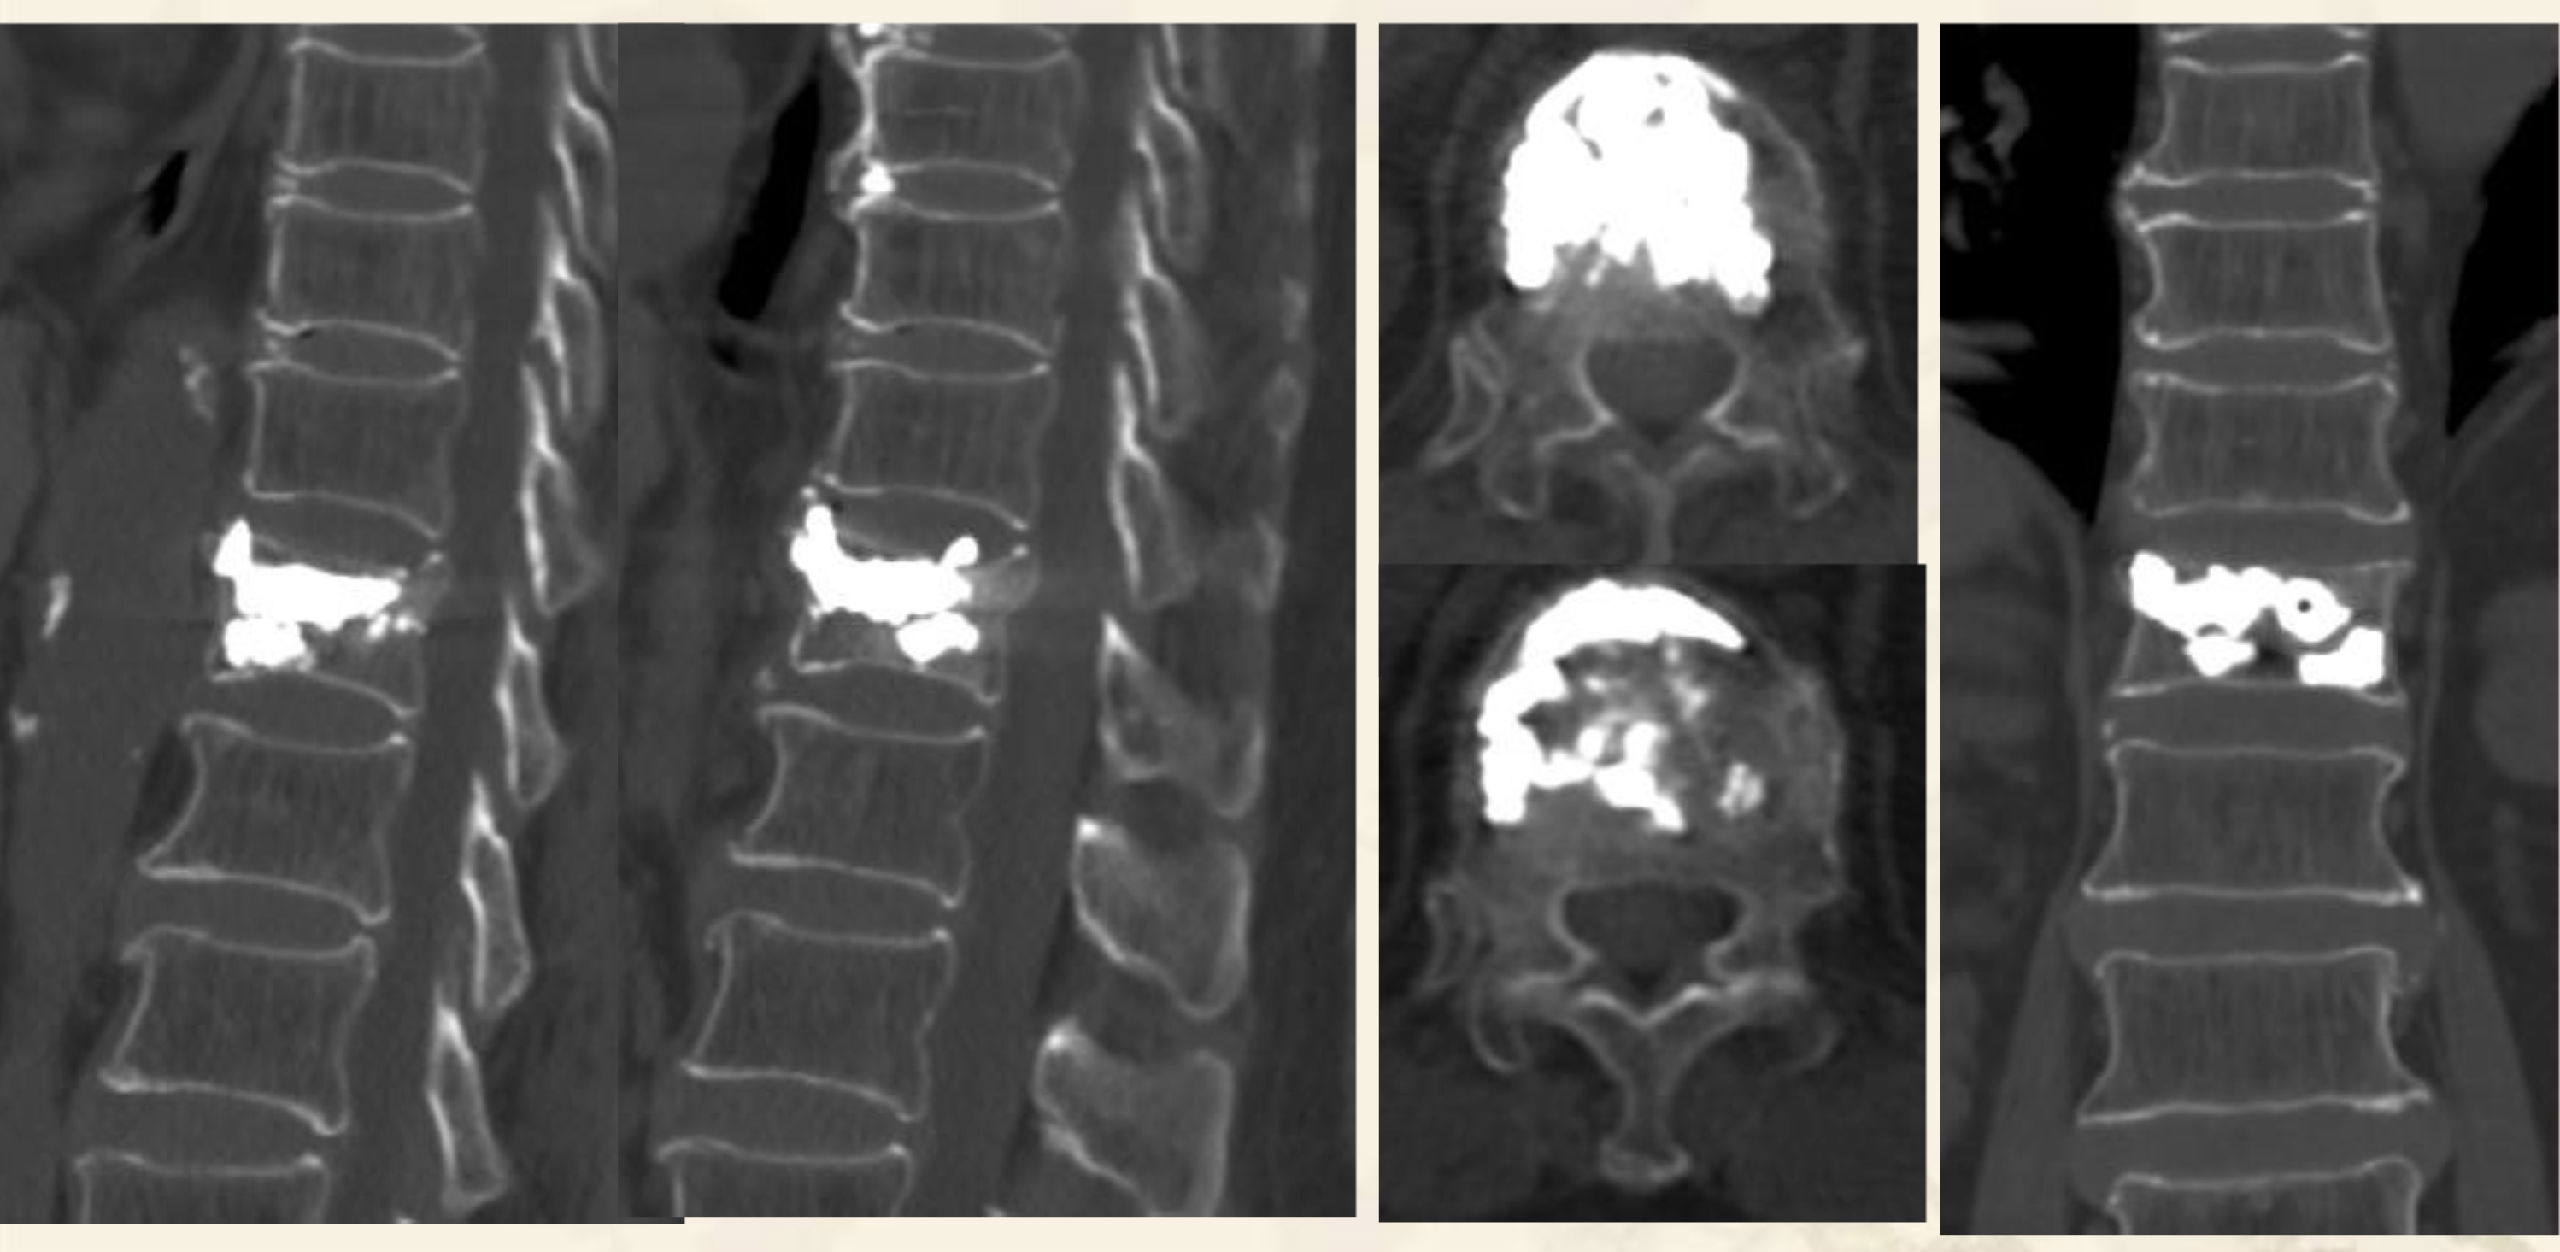

术前X线

术前MRI

术前CT

术后X线

术后CT